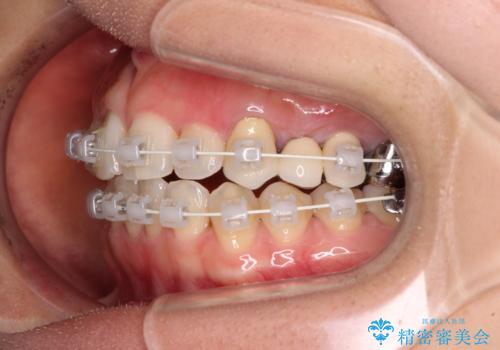

- 審美装置

装着されているブリッジを切断して矯正治療を行うことや、手間をかけずに早めに治療を終えたいとのことで、目立たないワイヤー装置による矯正治療を行うこととしました。

矯正治療中に上下前歯が接触しない時期があり、咬み合わせ改善のために期間がかかるのではないかと懸念されましたが、結果的には補綴治療も含めて1年以内の短期間で終えることができました。